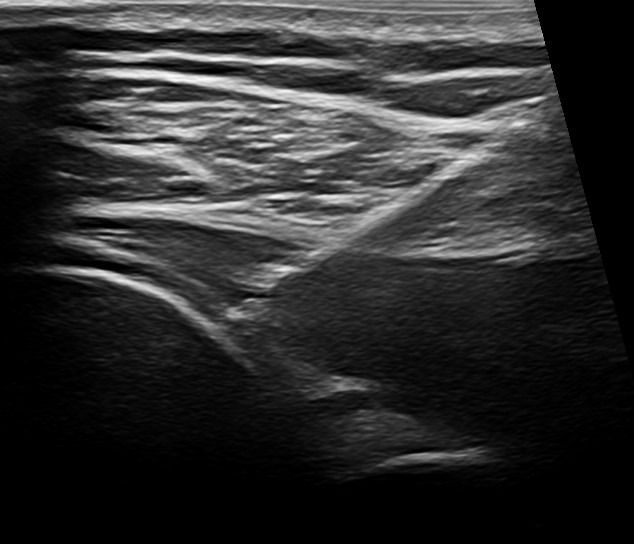

Παρότι η αρχική διάγνωση της Ασβεστοποιού Τενοντίτιδας μπορεί να γίνει και με απλή ακτινογραφία ώμου, το Υπερηχογράφημα είναι η ενδεδειγμένη μέθοδος απεικόνισης των ασβεστώσεων, καθώς παρέχει λεπτομερείς πληροφορίες για το μέγεθος, τη θέση τους και το στάδιο στο οποίο βρίσκονται.

Όταν οι ασβεστώσεις βρίσκονται στο στάδιο της ρευστοποίησης μπορούν να απεικονιστούν υπερηχογραφικά, αλλά να μην απεικονιστούν στην απλή ακτινογραφία. Επιπλέον, το Υπερηχογράφημα παρέχει τη δυνατότητα μελέτης των τενόντων ώστε να διαπιστωθεί αν συνυπάρχει άλλο πρόβλημα, όπως ρήξη του τένοντα.